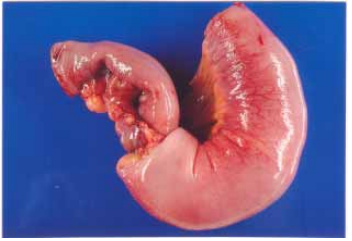

83 一名 25 歲女性因右上腹疼痛就醫。經過一系列的檢查後接受手術治療。附圖是她接受部分小腸切除 手術標本的外觀。下列何者是圖片所示最主要的病理變化?

(A)黏連(adhesion) (B)疝脫(hernia) (C)腸套疊(intussusception) (D)腸扭轉(volvulus)